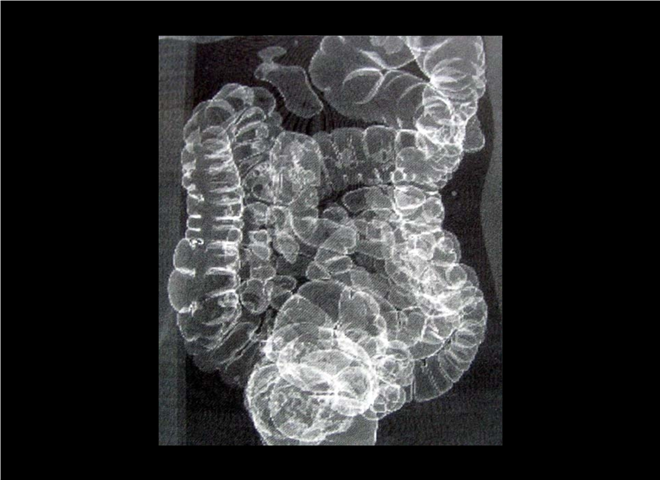

13_CT增强扫描